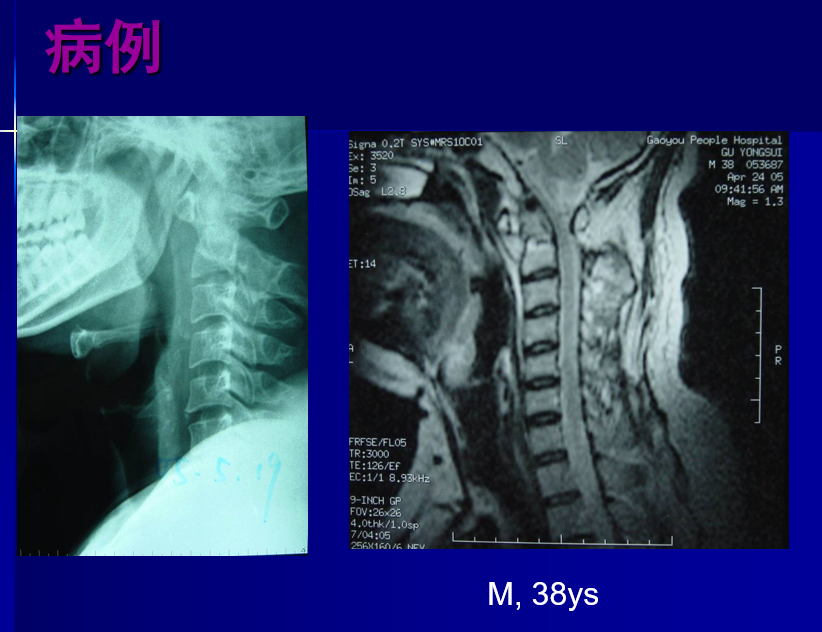

病例